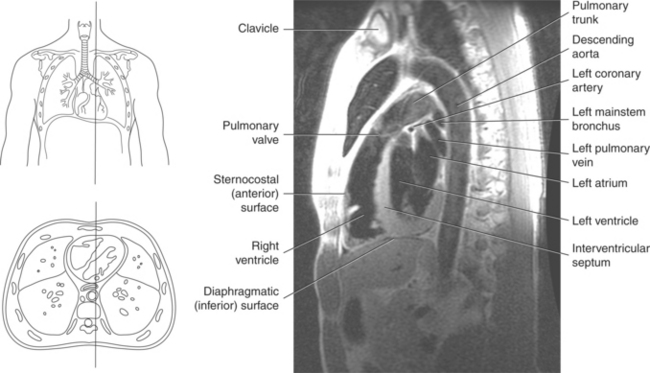

The heart is a hollow, four-chambered muscular organ located within the middle mediastinum. It is approximately the size of a large clenched fist and is situated obliquely in the chest with one third of its mass lying to the right of the median plane and two thirds to the left. The heart can be described as being roughly trapezoid shaped (Figure 6.33). The superficial relationships of the heart include the base, apex, three surfaces (sternocostal, diaphragmatic, pulmonary), and four borders (right, inferior, left, and superior). The broad base (posterior aspect) is the most superior and posterior portion of the heart. It is formed by both atria, primarily the left atrium, and gives rise to the great vessels. The apex is formed by the left ventricle and points inferiorly, anteriorly, and to the left. It is located at the level of the fifth intercostal space, just medial to the midclavicular line. The sternocostal (anterior surface) is formed primarily by the right atrium and right ventricle with a small contribution from the left ventricle. The diaphragmatic (inferior surface) rests on the central tendon of the diaphragm and is formed by both ventricles and a small portion of the right atrium. The pulmonary (left surface) is formed mainly by the left ventricle and fills the cardiac notch of the left lung. The borders of the heart represent the external surfaces of the cardiovascular silhouette in radiographic profile. The borders include the right border, formed by the right atrium and located between the superior and inferior venae cavae; the left border, formed by the apex of the heart or the left ventricle; the superior border, formed by the right and left atria; and the inferior border, which is formed primarily by the right ventricle with a small contribution from the left ventricle (Figures 6.33 through 6.35).

Blood travels to and from the heart through the great vessels, which include the aorta, pulmonary arteries and veins, and superior and inferior venae cavae (Figures 6.54 and 6.55). The aorta is the largest artery of the body and can be divided into the ascending aorta, aortic arch, and descending aorta. The ascending aorta begins at the base of the left ventricle at the level of the sternal angle, then curves superiorly and posteriorly as the aortic arch over the root of the left lung. The top of the aortic arch is approximately at T3 (Figures 6.56 and 6.57). The arch continues as the descending aorta posterior to the left bronchus and pulmonary trunk, on the left side of the vertebral body of T4 (Figures 6.58 and 6.59). The descending aorta passes slightly anterior and to the left of the vertebral column as it descends through the thoracic and abdominal cavities (Figure 6.60). While in the thoracic cavity, the descending aorta is commonly called the thoracic aorta, and while in the abdominal cavity, it is called the abdominal aorta. The pulmonary trunk is the origin of the right and left pulmonary arteries and lies entirely within the pericardial sac. It arises from the right ventricle and ascends in front of the ascending aorta, courses posteriorly and to the left, where it bifurcates at the level of the sternal angle (T4) into the right and left pulmonary arteries (Figures 6.61 through 6.63). The pulmonary trunk is attached to the aortic arch by a fibrous cord called the ligamentum arteriosum, the remnant of an important fetal blood vessel (ductus arteriosus) that links the pulmonary and systemic circuits during fetal development (Figures 6.54 and 6.61). The right pulmonary artery courses laterally, posterior to the ascending aorta and superior vena cava, and anterior to the esophagus and right mainstem bronchus, to the hilum of the right lung. At the root of the right lung, the right pulmonary artery divides into two branches, with the lower branch supplying the middle and inferior lobes and the upper branch supplying the superior lobe (Figures 6.61 through 6.64). The left pulmonary artery, shorter and smaller than the right, is also the most superior of the pulmonary vessels. It travels horizontally, arching over the left mainstem bronchus, and enters the hilum of the left lung just superior to the left mainstem bronchus (Figures 6.61 through 6.64). Within the lungs, each pulmonary artery descends posterolateral to the main bronchus and divides into lobar and segmental arteries, continuing to branch out and to follow along with the smallest divisions of the bronchial tree (Figures 6.61 and 6.64). Located inferior to the pulmonary arteries are the four pulmonary veins, two each (superior and inferior) extending from each lung to enter the left atrium (Figures 6.54, 6.55, 6.61, and 6.64 through 6.68). They commence in a capillary network along the walls of the alveoli, where they are continuous with the capillaries of the pulmonary arteries. The venous capillaries merge to form small vessels that unite successively to eventually form a single trunk for each lobe: three for the right and two for the left lung. Frequently the trunk from the middle lobe of the right lung unites with the trunk from the upper lobe, forming just two trunks on the right side prior to entering the left atrium. The right superior pulmonary vein collects blood from the upper lobe segments of the right lung and passes anterior and inferior to the right pulmonary artery, behind the superior vena cava. The right inferior pulmonary vein receives blood from the right lower lobes of the lung and crosses behind the right atrium to the left atrium (Figures 6.61 and 6.69 through 6.71). The left superior pulmonary vein receives blood from the left upper lobe of the left lung and courses anterior and inferior to the left main bronchus as it enters the left atrium. The left inferior pulmonary vein drains the inferior lobe of the left lung and passes toward the left atrium anterior to the bronchi (Figures 6.61 and 6.72 through 6.74). The pulmonary veins course more horizontally than the pulmonary arteries and are ultimately oriented toward the left atrium. At the root of the lungs, the pulmonary veins are anterior to the pulmonary arteries, which are anterior to the bronchus. While within the lungs, the branches of the pulmonary arteries are anterior to the bronchi, which are anterior to the pulmonary veins. The superior and inferior venae cavae are the largest veins of the body. The superior vena cava is formed by the junction of the brachiocephalic veins, posterior to the right first costal cartilage, and carries blood from the thorax, upper limbs, head, and neck (Figure 6.24). As it travels inferiorly, it is located posterior and lateral to the ascending aorta before entering the upper portion of the right atrium (Figures 6.54 through 6.59). The inferior vena cava is formed by the junction of the common iliac veins in the pelvis and ascends the abdomen to the right of the abdominal aorta and anterior to the vertebral column. It passes through the caval hiatus of the diaphragm and almost immediately enters the inferior portion of the right atrium (Figures 6.75 and 6.76).

Figure 6.60 Sagittal, T1-weighted MR scan with aortic arch and descending aorta.

Key: ar, aortic arch; da, descending aorta; mbr, mainstem bronchi; rPA, right pulmonary artery; ab, aortic bulb; la, left atrium; rv, right ventricle.